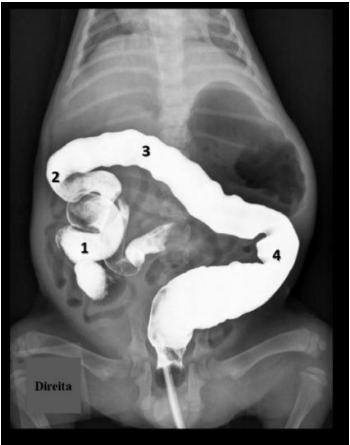

Observe a radiografia a seguir.

A partir da observação dessa radiografia, quais são as estruturas identificadas na imagem pelos números 1, 2, 3 e 4, respectivamente?